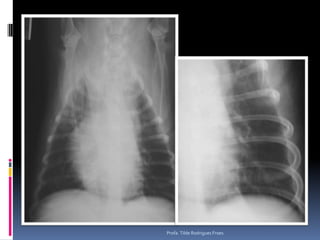

Exame radiográfico torácicoNossa rotina – nossos velhinhos...Pesquisa de metástasesColapso de traquéiaInsuficiência cardíacaBronquite crônica *Análise interobservadorSempre mais de um observador analisa o filme radiográfico torácico (difícil) Profa. Tilde Rodrigues Froes

Ex colapsoProfa. Tilde Rodrigues Froes

Exame radiográfico torácicoNossarotina – nossos velhinhos...Pesquisa de metástasesColapso de traquéiaInsuficiência cardíacaBronquite crônica *Análise interobservadorSempre mais de um observador analisa o filme radiográfico torácico (difícil) Profa. Tilde Rodrigues Froes

Ex colapsoProfa. TildeRodrigues Froes